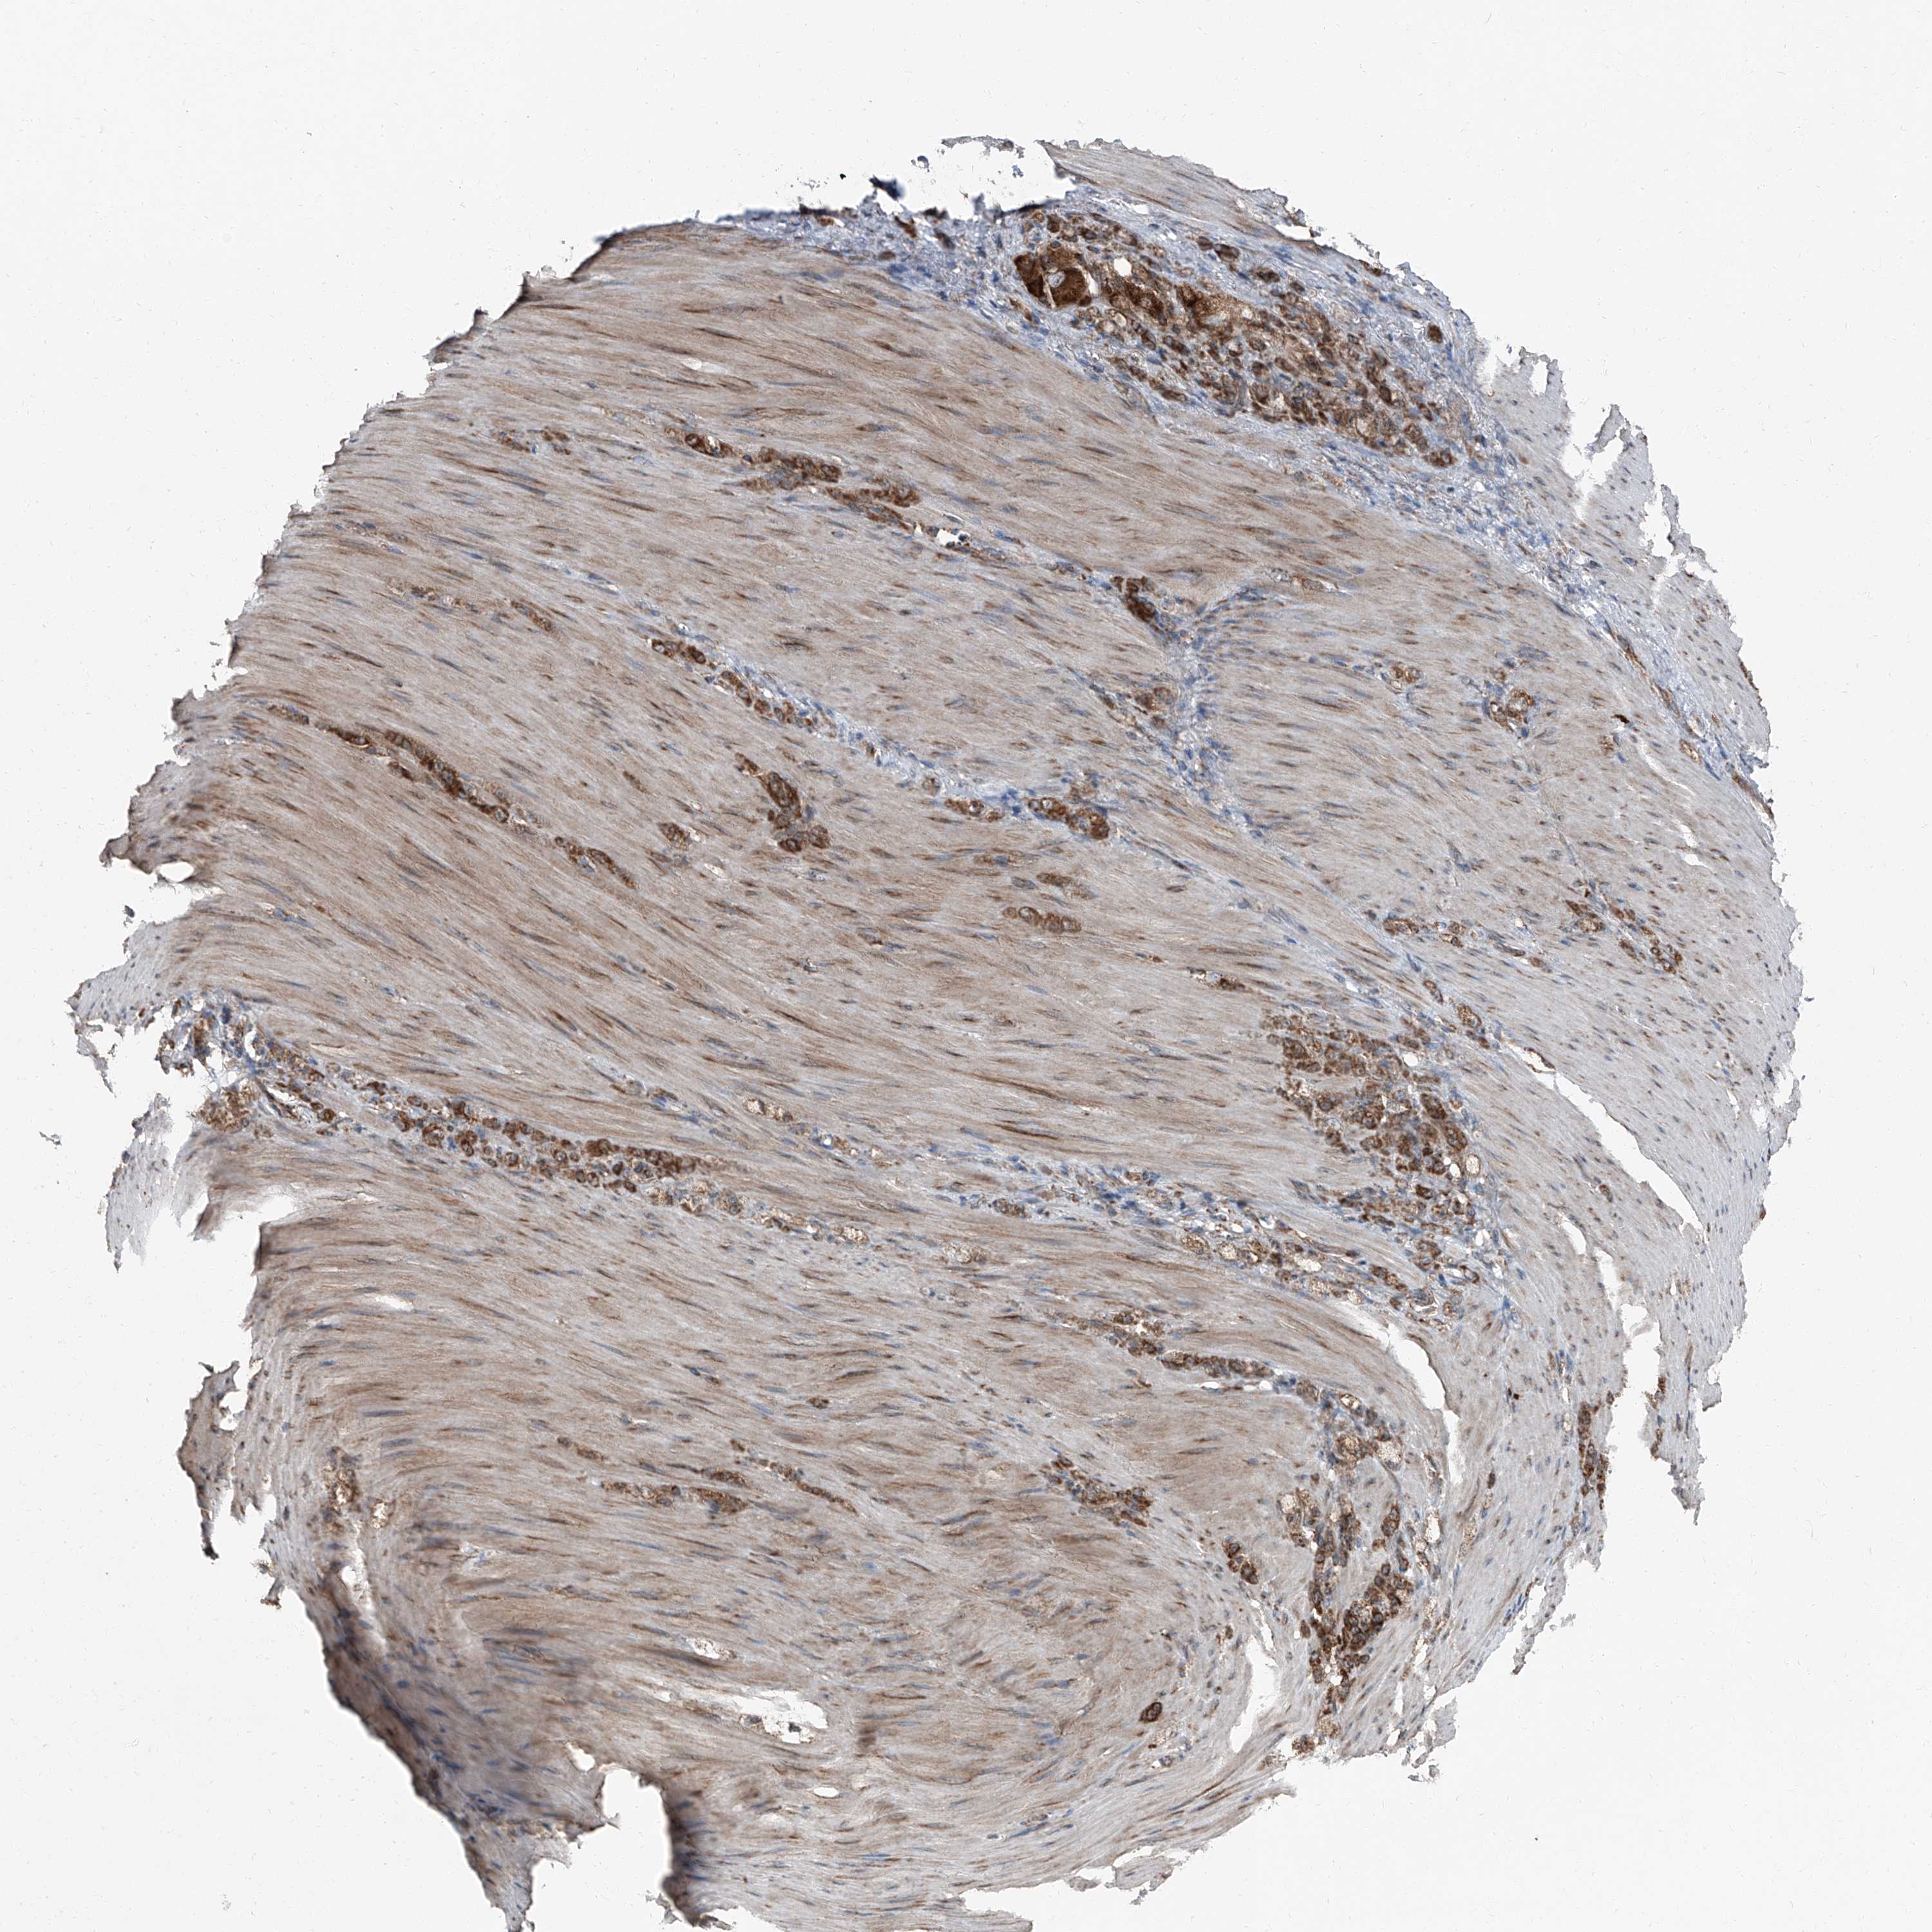

STOMACH CANCER - Protein expressioni

A mouse-over function shows sample information and annotation data. Click on an image to view it in a full screen mode. Samples can be filtered based on level of antibody staining by selecting one or several of the following categories: high, medium, low and not detected. The assay and annotation is described here.

Antibody stainingi

Antibody staining in the annotated cell types in the current human tissue is reported as not detected, low, medium, or high, based on conventional immunohistochemistry profiling in selected tissues. This score is based on the combination of the staining intensity and fraction of stained cells.

Each image is clickable and will lead to virtual microscopy that enables deeper exploration of all samples and also displays staining intensity scores, fraction scores and subcellular localization as well as patient and tissue information for each sample.

Antibody HPA028516

Antibody HPA073571

Staining

High

Medium

Low

Not detected

Intensity

Strong

Moderate

Weak

Negative

Quantity

>75%

75%-25%

<25%

None

Location

Nuclear

Cytoplasmic/membranous

Cytoplasmic/membranous,nuclear

Adenocarcinoma, NOS

Adenocarcinoma, High grade